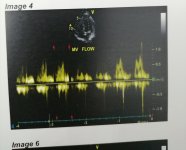

عملت ايكو هل في حاجه في الايكو تستدعي الذهاب لطبيب قلب و ارجو شرحها ان وجدت؟ و شكرا

عملت ايكو هل في حاجه في الايكو تستدعي الذهاب لطبيب قلب و ارجو شرحها ان وجدت؟ و شكرا